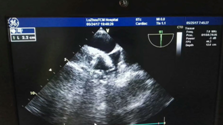

近日, 我院專家團(tuán)隊(duì)通力配合,成功為一名78歲高齡的患者實(shí)施了左心耳封堵術(shù)。專家在患者左心耳置入了一個(gè)封堵器,從而有效地預(yù)防了患者發(fā)生房顫卒中的風(fēng)險(xiǎn),據(jù)悉,這是川南地區(qū)成功開展的首例經(jīng)食道超聲指引下的“左心耳封堵術(shù)”。????? ?手術(shù)中?78歲高齡老人房顫致血栓???服藥無效??? ?? 江陽區(qū)一...